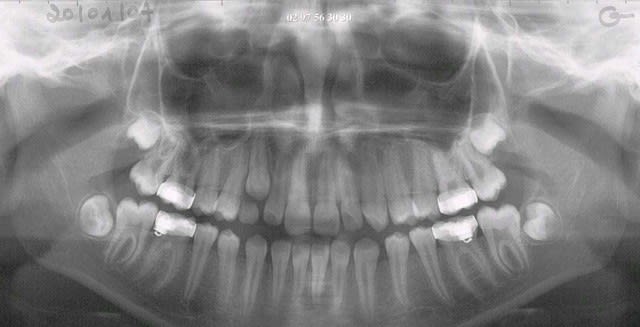

voilà:eln seul 9 mois en 2003 puis,perdue de vue(rvms)

eln n°2 +2LB déc 2005

début 2008,quadhélix en 0.28,pour vestibuler la 2,ce qui est fait